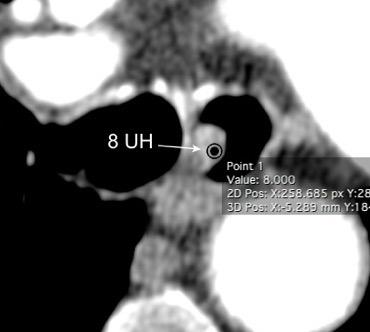

Timoma quístico

Linfangioma

Quistes. (18-25% de todas las masas)

Tímico

Pericárdico/Esofágico

Hidatídico

Meningocele lateral

Teratoma

Hematoma/Seroma /Absceso/Secuestro

Seudoquiste pancreático

Ascitis en hernia hiatal

Quiste celómico alto Vargas D et al. Cystic lesions of the mediastinum. Semin Ultrasound CT MRI. 2016